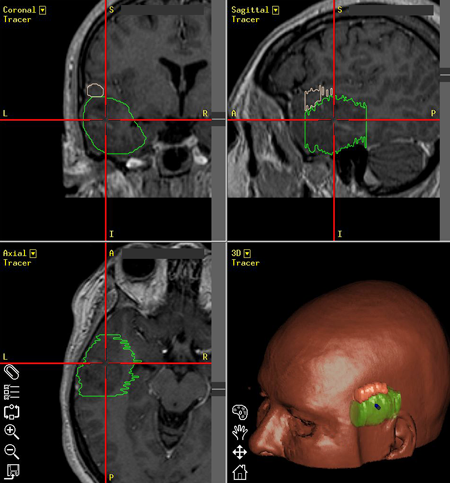

Η μέθοδος συνίσταται στην δημιουργία μιας τρισδιάστατης ανασύνθεσης με ψηφιακό τρόπο ενός μοντέλου του εγκεφάλου του ασθενούς (με βάση τις πληροφορίες που λαμβάνονται από μια μαγνητική, ή σπάνια αξονική, τομογραφία του εγκεφάλου που πραγματοποιείται με ειδικό πρωτόκολλο), και στην χρήση αυτού του μοντέλου στο χειρουργείο για την ακριβή εύρεση της θέσης της χωροκατακτητικής εξεργασίας. Η ανασύνθεση των εικόνων γίνεται με την βοήθεια υπολογιστή και ειδικού εξοπλισμού και το ίδιο ισχύει για την ταύτιση του μοντέλου με την πραγματική θέση της κεφαλής στο χειρουργείο.

Συγκεκριμένα, ο ασθενής πρέπει να υποβληθεί σε μια μαγνητική τομογραφία του εγκεφάλου με ειδικό πρωτόκολλο, πριν από την χειρουργική επέμβαση. Ο χρόνος της πραγματοποίησης της μαγνητικής τομογραφίας καλό είναι να μην υπερβαίνει την 1 εβδομάδα πριν την επέμβαση. Οι εικόνες της απεικονιστικής εξέτασης εισάγονται στον ειδικό εξοπλισμό του νευροπλοηγού και δημιουργείται ένα τρισδιάστατο ανατομικό μοντέλο του εγκεφάλου του ασθενούς με όλες της πληροφορίες της μαγνητικής τομογραφίας.